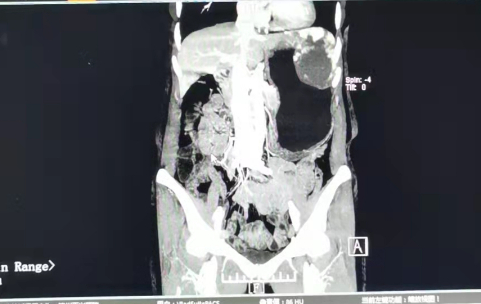

患者林阿姨,為一62歲女性,在我院行健康檢查后,發(fā)現(xiàn)肝左外葉有一巨大血管瘤,大小約63*90mm,發(fā)愁的林阿姨緊急求助于我院普外科。

由于該血管瘤處于患者腹部外側,若在生活中受到撞擊等意外,恐會引起大出血,甚至會導致休克、死亡,后果不堪設想,相當于一顆安在人體里的“不定時炸彈”,需要及時進行手術治療。

12月31日下午,手術正式開始。李建國副院長率領手術團隊,僅在患者肚臍處切開一個3cm左右的小切口,將手術器械同時經(jīng)過該切口置入腹腔,利用嫻熟的微創(chuàng)手術技術,充分游離、精準切除,最后通過小切口完整地取出標本。

手術僅用時1小時15分鐘,出血約100毫升。該手術方式對腹壁創(chuàng)傷小,降低了切口相關并發(fā)癥,也減輕了術后疼痛,將使得術后恢復更快。